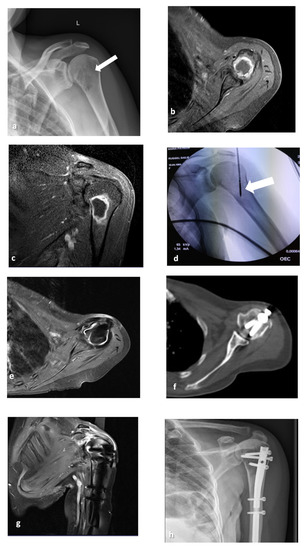

2.2. MWA Technique

2.3. Surgical Technique